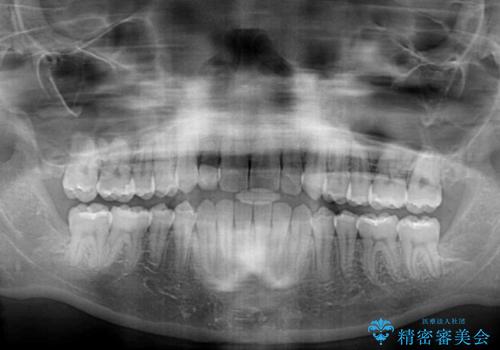

レントゲン写真上では、矯正治療前後で歯根長さに大きな違いはなく、抜歯を回避することができました。

上顎内側に転位している前から2番目の歯は移動が難しく、無理矢理歯根全体を動かそうと設計すると、歯肉退縮・歯髄壊死・歯根吸収といった危険性が増すため、無難なゴールにて治療を終えることとなりました。